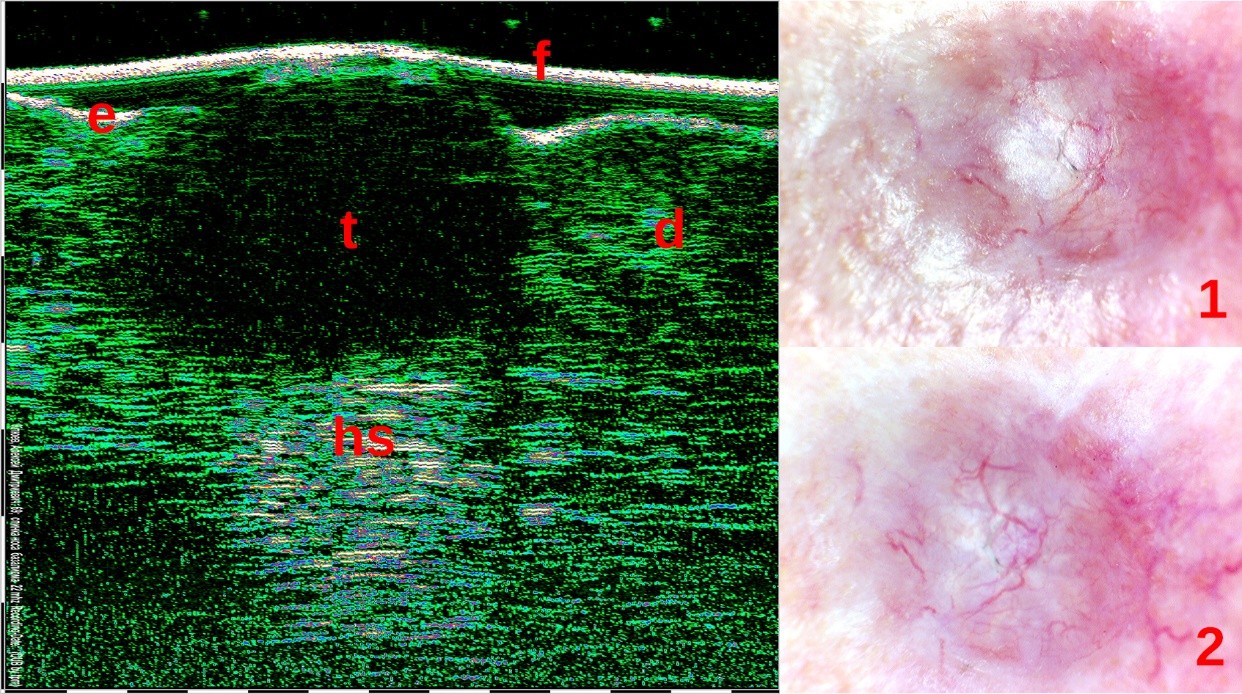

Η διαφοροποίηση μεταξύ των Υπερτροφικών Ουλών (1η εικόνα) και των Χηλοειδών (2η εικόνα) με τη βοήθεια του Υπέρηχου Υψηλής Συχνότητας.

Οι μετρήσεις ουλών με HFUS και η ανάλυση των μοτίβων χρησιμοποιήθηκαν με επιτυχία για τη διαφοροποίηση των νορμοτροφικών, υπερτροφικών, χηλοειδών και ατροφικών ουλών. Αυτές οι κλινικές πληροφορίες είναι ζωτικής σημασίας για την ορθή θεραπεία και αποκατάσταση των ουλών.

Οι μετρήσεις ουλών HFUS και η ανάλυση των μοτίβων χρησιμοποιήθηκαν με επιτυχία για τη διαφοροποίηση των νορμοτροφικών, υπερτροφικών, χηλοειδών και ατροφικών ουλών. Αυτές οι κλινικές πληροφορίες είναι ζωτικής σημασίας για την ορθή θεραπεία και αποκατάσταση των ουλών.

Η διαφοροποίηση μεταξύ των υπερτροφικών (αριστερά) και των χηλοειδών ουλών (δεξιά).